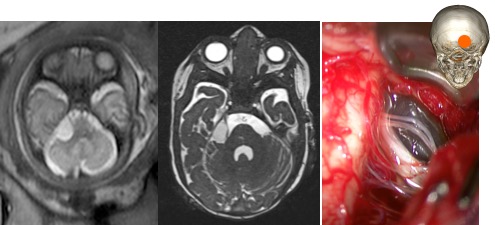

les kystes du plexus choroïde

ils sont de constatation assez banale et généralement non évolutifs. on les trouve tout le long du sillon choroïdien, ils peuvent donc occuper chacun des 4 ventricules ainsi que l’angle ponto-cérébelleux.

le plus souvent, ils ne nécessitent aucune prise en charge.

dans de très rares cas, ils s’associent à un blocage du foramen inter-ventriculaire de Monro, et peuvent nécessiter une intervention (fenestration endoscopique) à la naissance.